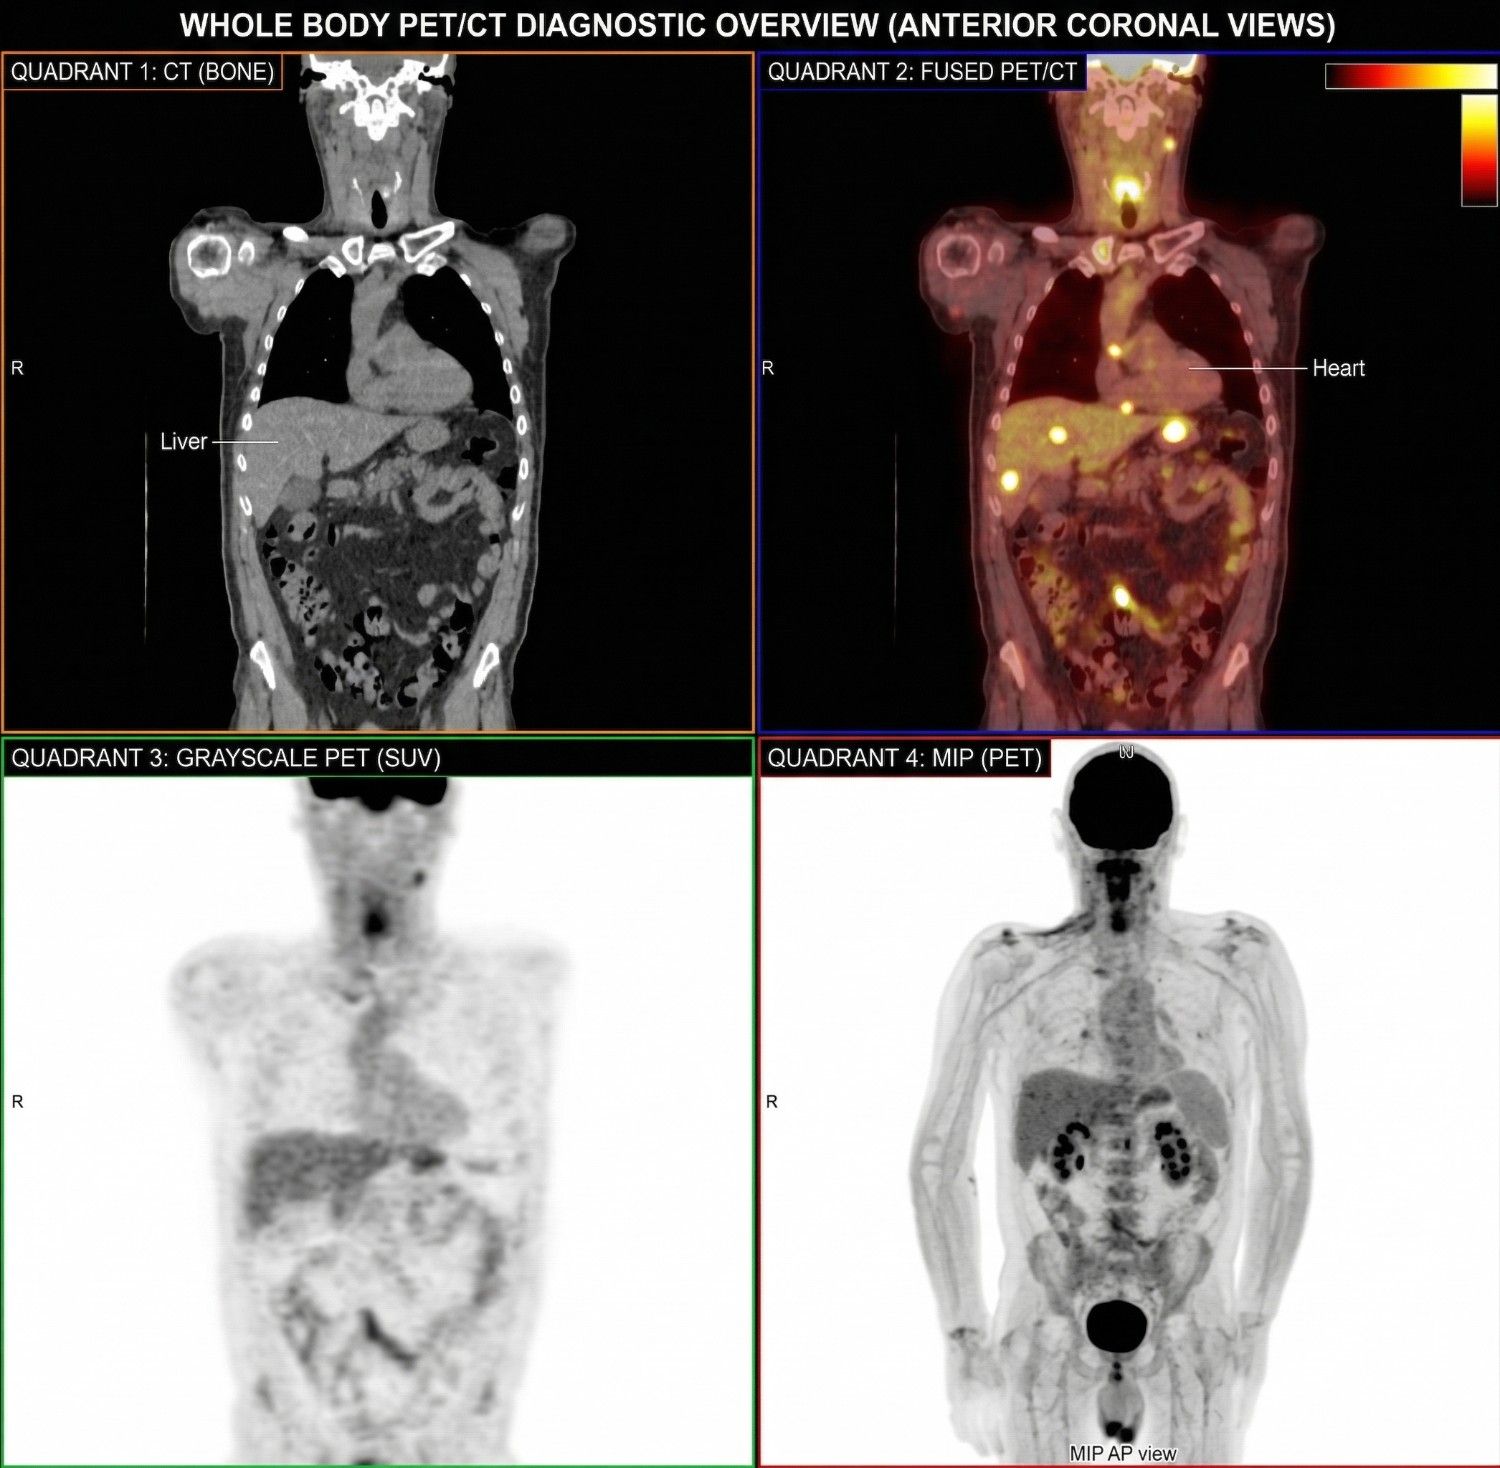

Nuclear Medicine

We also extend our expertise to Nuclear Medicine, offering comprehensive reporting services for all types of gamma scans and PET scans. From oncological imaging to a wide range of functional studies, our experienced Nuclear Medicine physicians ensure accurate and reliable interpretations. Beyond reporting, their specialized expertise supports optimal scan planning, enabling our centers to maximize diagnostic yield and extract clinically meaningful insights from every study.

PET-CT Bone Scan Thyroid Studies Renal Scintigraphy Cardiac Stress